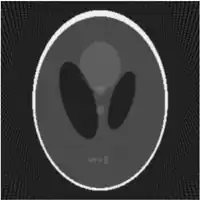

| Fantasma de Shepp-Logan; Transformada de Radon; y Transformada de Radon inversa | ||

Existe un algoritmo inverso de la transformada de Radon computacionalmente eficiente para el caso bidimensional llamado retroproyección filtrada. Primeramente consideremos el operador adjunto de :

lo que significa que la imagen original puede ser recuperada del 'sinograma' aplicando un filtro rampa (sobre la variable ) y entonces retroproyectando. Como que el paso de filtrado puede ser implementado de forma eficiente (mediante técnicas de procesamiento digital de señales) y la retroproyección no es más que una acumulación de valores en los píxeles de la imagen, resulta un algoritmo altamente eficiente, por lo que se trata de un algoritmo ampliamente usado.